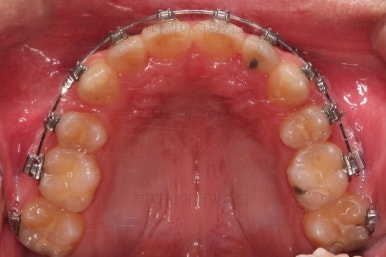

먼저 장치를 부착하고요.

환자분이 선택하신 장치는 자가결찰 메탈장치 입니다.

메탈이라고 모두 구시대적 장치는 아니에요. 자가결찰인지 아닌지가 구세대나 아니냐를 결정하는 기준이에요.

적절한 시기에 발치를 해주고요.

발치 공간을 이용해서 치열을 가지런하게 해줍니다.

가지런하게만 해도 발치공간이 거의다 없어져가요.